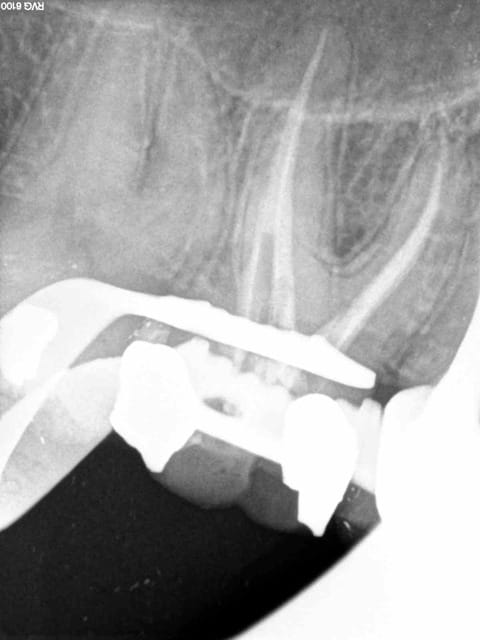

17/11/2014 à 21h21

Ou encore celle ci : le mv2 m'a un peu fait chier. Spécial dédicace pour alapex, je le sens un peu joueur sur les endos molaires sup ces temps ci. -))))

1 jiki3t - Eugenol

2 unsnvj - Eugenol

3 msykxk - Eugenol

4 hrzhzs - Eugenol

5 gcfl3e - Eugenol